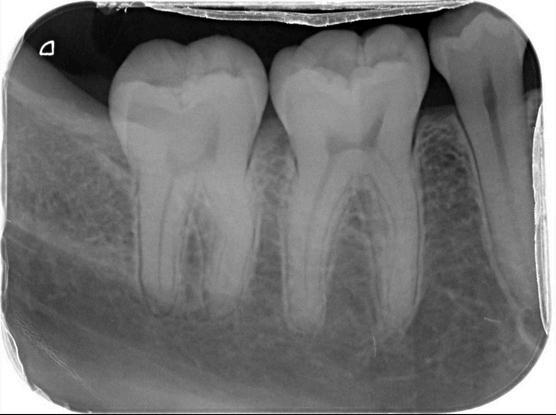

ฟนและกระดกขากรรไกรมหลายสวนทซอนอยใตเหงอก และเมอ เกดความผดปกตขนอาจจะไมสามารถมองเหนไดเพยงจากการ

การสงถายภาพรงส เพอการวนจฉยโรคในชองปากมความสาคญอยางยง

โดยเฉพาะในการประเมนรอยผของฟน ในผปวยทไมเคย ตรวจสขภาพชองปากมากอนหรอผทมาพบทนตแพทย เป นครงแรก

นอกเหนอจากการตรวจรอยผในชองปากจากการตรวจด

โดยตรงแลว ทนตแพทยจะพจารณาการถายภาพรงสใน

ชองปาก เพอชวยตรวจหาบรเวณรอยผดานประชดฟน (proximal caries)